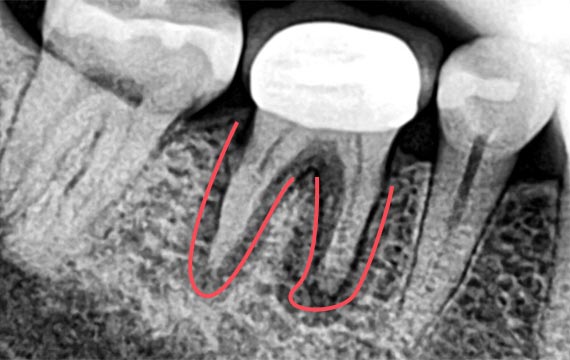

시술 전후 비교

BEFORE

down

AFTER